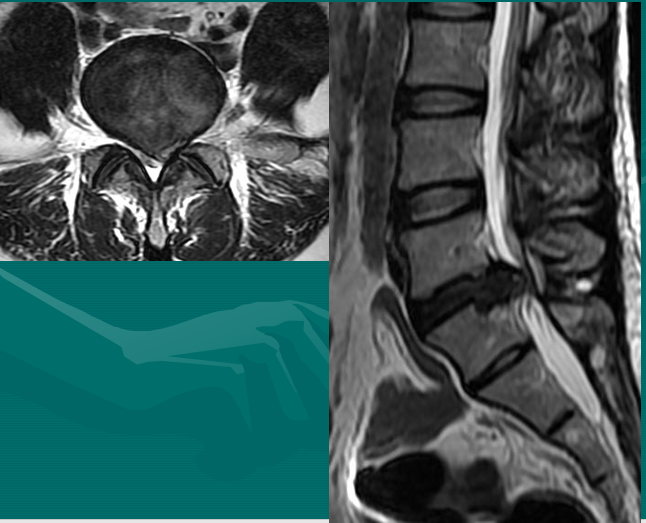

一个健康的45岁男性的L4椎间盘的轴状面观。

髓核区及周围的纤椎环区。

靠近L5神经根的椎间盘后缘的凹度,这是正常健康椎间盘的象征。

L4发出神经根更靠侧方一点。这就不难理解为什么如果有大的椎间盘突出或椎管狭窄,发出神经根L4及过往神经根L5将同时受压。

在此图中,可清楚地看到悬挂在硬膜囊内的细小的神经根(L5神经根及S1神经根),它们以不完全有绪地状态排列着。注意,神经孔是很开阔的(浅黄色区),表明没有因邻近椎间关节问题形成在的椎管狭窄。T2加权象对于察看退化性椎间盘病是最好的,因为T2像将富含水份的结构表现为亮白色, 含水少的区域表现为黑色。